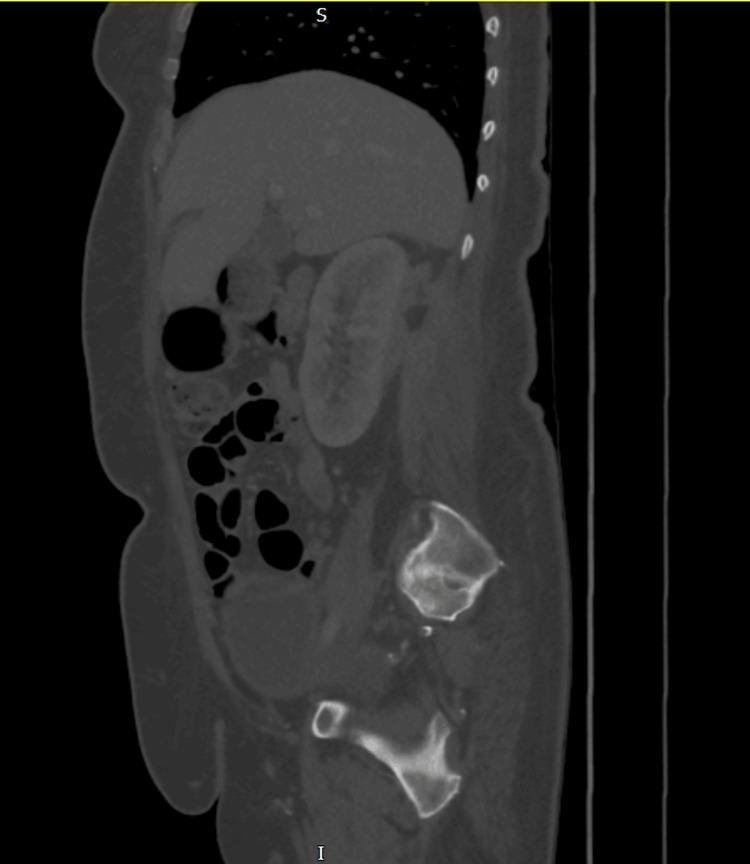

Iliopsoas abscess is a rare infection that presents with a triad of fever, back pain, and hip pain. However, due to the anatomical proximity of the psoas muscle to various structures, an abscess in this region can manifest with nonspecific symptoms, leading to potential misdiagnosis and delayed diagnosis, which can be fatal. We report a case of a 54-year-old female who presented to the emergency department with right-sided flank pain and symptoms resembling lower motor neuron disorder. Initial investigations were inconclusive until an MRI revealed a large retroperitoneal collection in the right perinephric space and iliopsoas muscle, likely of urological origin, with no spinal abnormalities. Intravenous gentamicin was initiated. A subsequent contrast-enhanced CT scan of the abdomen and pelvis confirmed a right posterior perinephric collection. Ultrasound-guided drainage was performed, and a pigtail catheter was placed in situ for continuous drainage along with targeted antibiotics based on culture and sensitivity.

髂腰肌脓肿是一种罕见的感染性疾病,表现为发热、背痛和髋部疼痛三联征。然而,由于腰大肌与各种结构在解剖位置上相邻,该区域的脓肿可能表现为非特异性症状,导致潜在的误诊和诊断延迟,这可能是致命的。我们报告一例54岁女性,因右侧胁腹疼痛及类似下运动神经元疾病的症状就诊于急诊科。最初的检查结果不明确,直到磁共振成像(MRI)显示右肾周间隙和髂腰肌有一个大的腹膜后积液,可能源于泌尿系统,且无脊柱异常。开始静脉注射庆大霉素。随后的腹部和盆腔增强CT扫描证实右肾后有积液。进行了超声引导下引流,并置入一根猪尾导管进行持续引流,同时根据培养和药敏结果使用针对性抗生素。